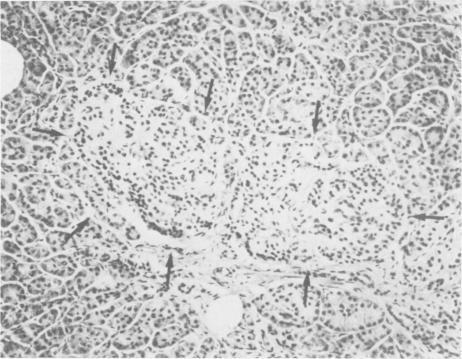

Total or near total pancreatectomy is the surest way to relieve the pain of chronic pancreatitis but is rarely applied because the metabolic consequences are so severe. For most patients drainage procedures are applicable, but pancreatectomy may be the only alternative for small duct disease or where procedures to improve duct drainage have failed. Preservation of endocrine function is a major problem in patients who require pancreatectomy. Experiments in pancreatectomized dogs have shown that intrasplenic or intraportal transplantation of unpurified pancreatic islet tissue dispersed by collagenase digestion can prevent diabetes. We have applied this technique to ten patients with chronic pancreatitis, small ducts, and intractable pain. The entire pancreas of > 95% of the pancrease was excised, minced, dispersed by collagenase digestion and infused into the portal vein < 2 1/2 hours after removal. Mean (+/- SD) rise in portal pressure was 17 +/- 8 cm of water. Liver function tests were altered minimally. All patients were relieved of pain. One patient died of a complication not related to the islet autotransplant; viable islets were identified in the liver at autopsy. Of the remaining nine patients, three have been insulin independent for 1, 9, and 38 months. One patient was insulin indpendent for 15 months and now takes 12 units of insulin daily. Three have nonketosis prone diabetes (tested by insulin withdrawal) and take 15--30 units of insulin per day. C-peptide studies in these patients show that functioning islets are present. Two patients are diabetic and require 35 and 60 units of insulin per day. In eight of nine patients tested serum insulin concentrations fell to undetectable levels during the interval between pancreatectomy and islet transplantation. Serum insulin levels during the first few hours after islet transplantation predicted success. In the insulin independent or in the patients with mild diabetes, insulin levels were persistently greater than or equal to 6 microU/ml. In the other two patients, the increase in insulin concentration was not sustained. Islet tissue preparation from a diseased pancreas is difficult. The surgeon and the patient must still be willing to accept diabetes for relief of pain when performing this operation. In some patients, however, islet autotransplantation can prevent or partially ameliorate diabetes after pancreatectomy, and preservation of endocrine function is worthwhile.

全胰切除术或近全胰切除术是缓解慢性胰腺炎疼痛最可靠的方法,但很少应用,因为其代谢后果非常严重。对于大多数患者而言,引流手术是可行的,但对于小导管疾病或改善导管引流的手术失败的情况,胰切除术可能是唯一的选择。对于需要进行胰切除术的患者,保留内分泌功能是一个主要问题。对胰腺切除的狗进行的实验表明,通过胶原酶消化分散的未纯化胰岛组织进行脾内或门静脉内移植可以预防糖尿病。我们已将此技术应用于10例患有慢性胰腺炎、小导管和顽固性疼痛的患者。切除了超过95%的胰腺,切碎,经胶原酶消化分散,并在切除后不到2个半小时内注入门静脉。门静脉压力平均(±标准差)升高17±8厘米水柱。肝功能检查仅有轻微改变。所有患者的疼痛均得到缓解。1例患者死于与胰岛自体移植无关的并发症;尸检时在肝脏中发现了存活的胰岛。其余9例患者中,3例已分别在1个月、9个月和38个月内无需胰岛素治疗。1例患者曾在15个月内无需胰岛素治疗,现在每天注射12单位胰岛素。3例有非酮症倾向糖尿病(通过停用胰岛素检测),每天注射15 - 30单位胰岛素。对这些患者进行的C肽研究表明存在有功能的胰岛。2例患者患有糖尿病,每天需要35和60单位胰岛素。在接受检测的9例患者中的8例中,血清胰岛素浓度在胰切除术和胰岛移植之间的间隔期降至无法检测的水平。胰岛移植后最初几个小时的血清胰岛素水平可预测手术是否成功。在无需胰岛素治疗或患有轻度糖尿病的患者中,胰岛素水平持续大于或等于6微单位/毫升。在另外2例患者中,胰岛素浓度的升高未持续。从患病胰腺制备胰岛组织很困难。在进行此手术时,外科医生和患者仍必须愿意接受糖尿病以缓解疼痛。然而,在一些患者中,胰岛自体移植可以预防或部分改善胰切除术后的糖尿病,并且保留内分泌功能是值得的。